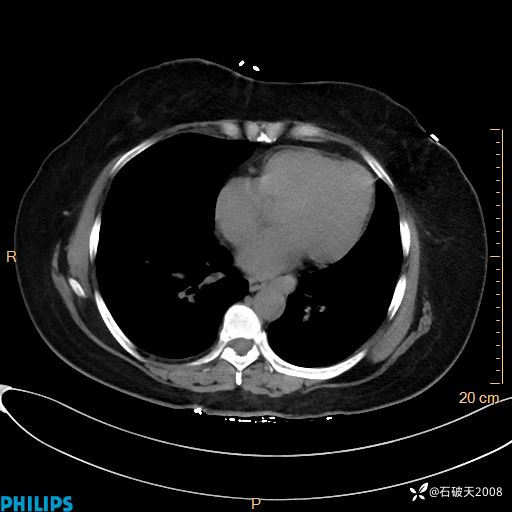

肺结节病?纵膈型肺癌?淋巴瘤?有点意思,欢迎围观

女 52岁 主 诉:咳嗽10余天,咳痰2天。

纵隔窗

动脉期